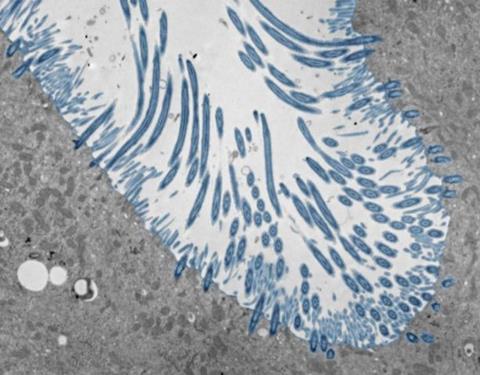

To do so, the researchers created lab-grown human nasal tissue. They cultured human nasal stem cells for four weeks while exposing the top surface to air. Under these conditions, the stem cells differentiated into a tissue with many of the cell types that are found in the human nasal passages and lining of the lung airways, including cells that produce mucus and cells with cilia—moving hair-like structures that sweep mucus out of the lungs.